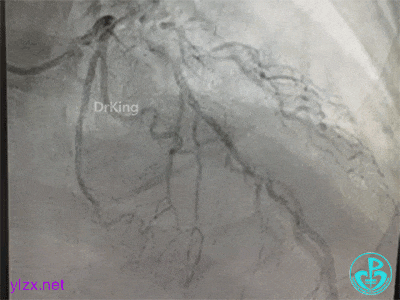

更换指引导管,导丝分别进入前降支和回旋支,球囊分别扩张前降支开口和回旋支开口,IVUS确认左主干及分支开口病变,前降支中段植入支架,对角支开口球囊扩张。

左主干分叉病变采取Crush双支架术式,回旋支开口植入支架,前降支开口球囊挤压后左主干到前降支植入支架(Crush双支架术式)。

导丝Rewire回旋支,非顺应性球囊分别后扩张前降支和回旋支支架,对吻扩张。